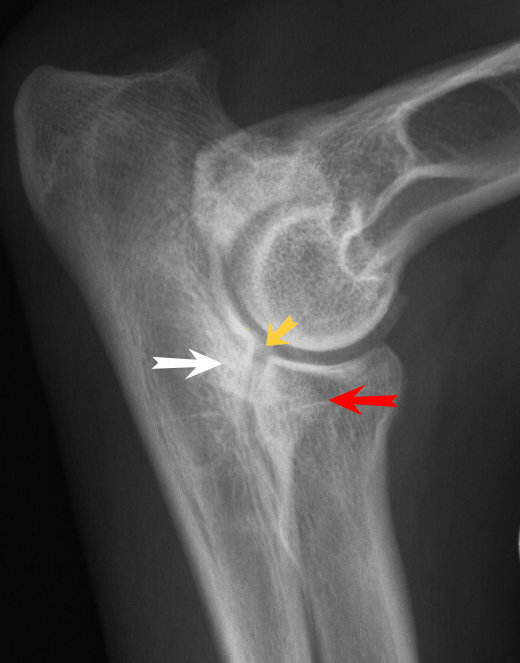

• A 4-year-old male neutered Labrador is presented to you with ongoing bilateral forelimb lameness. He is otherwise healthy, and no other abnormalities were found on general clinical examination. Crepitus was felt on manipulation on both elbow joints. You decide to take radiographs of both elbow joints. What is the main disease process resulting in the forelimb lameness in this case?

fragmented medial coronoid process